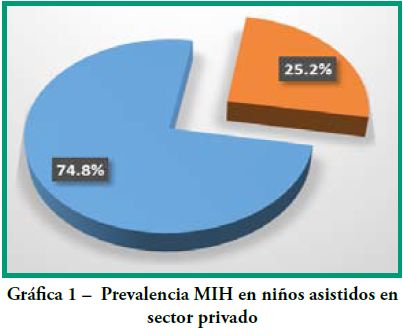

Los resultados intragrupo se representan en las Gráficas 1-6.

Prevalencia MIH según lugar de asistencia

Grupo 1 Sector Privado:

n=163 niños (41 se diagnosticaron con MIH),

Edad promedio 10.43 ± 2.79

La prevalencia de MIH fue de 25.2%. (Gráfica 1)